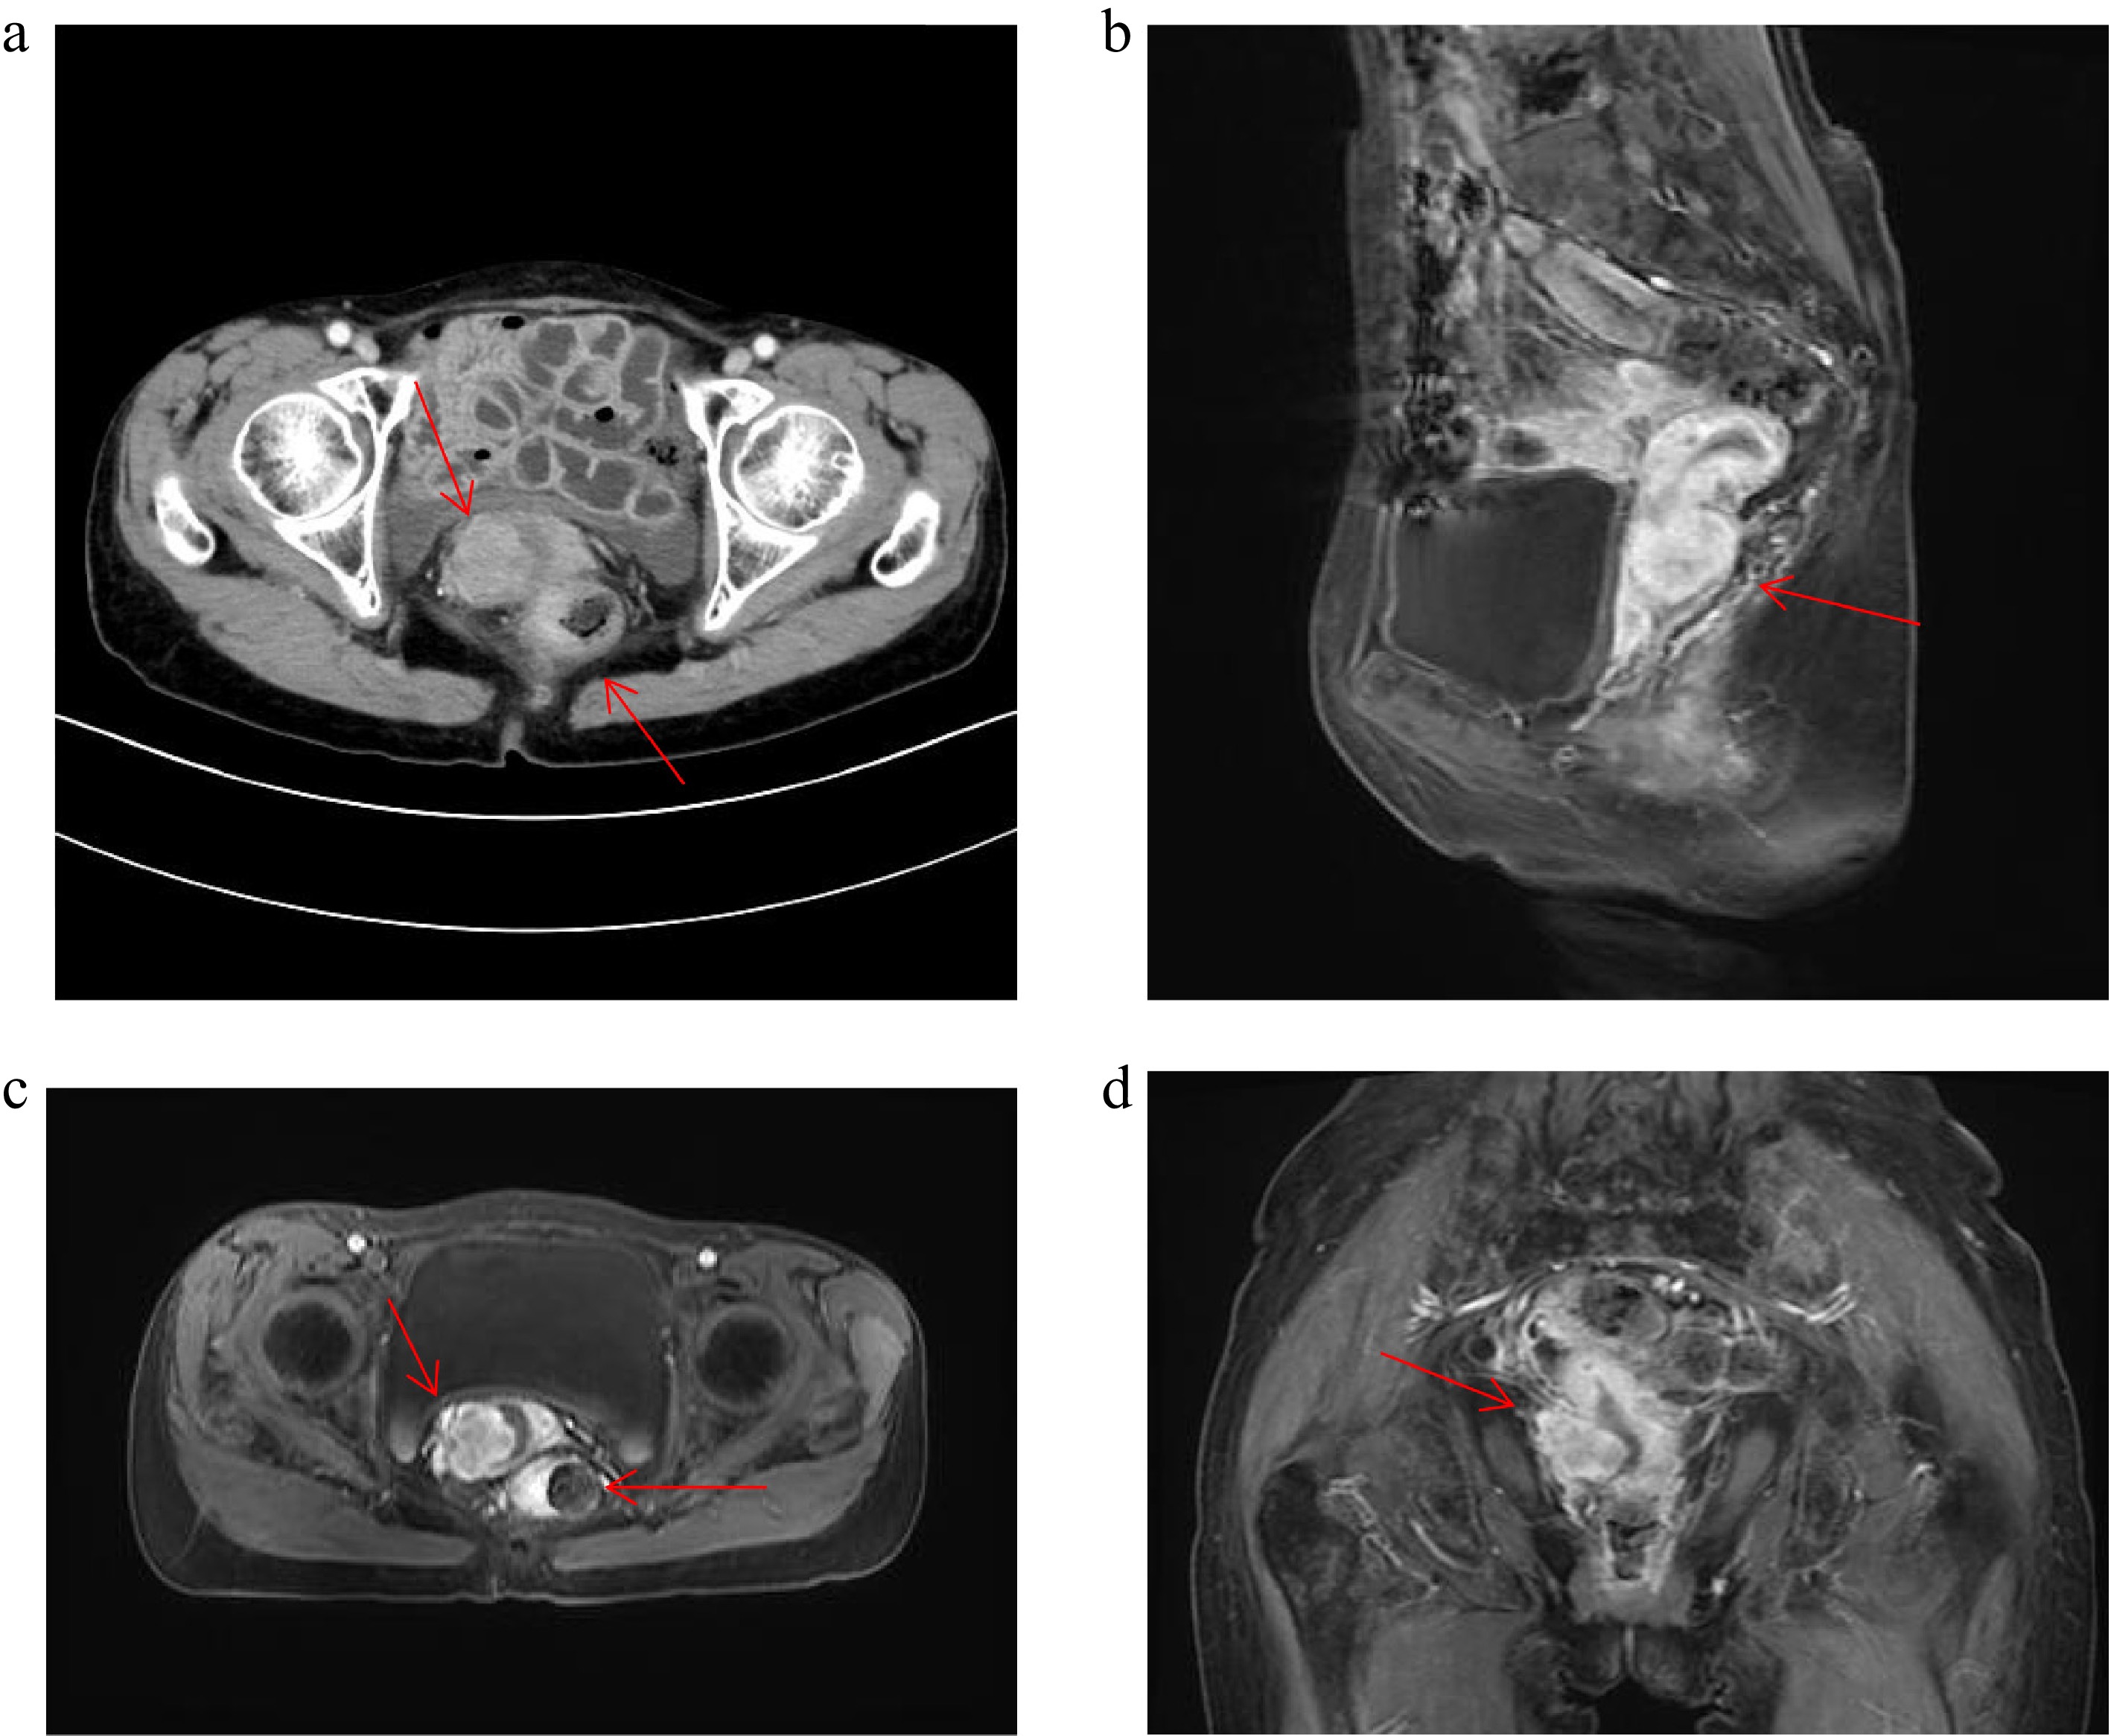

Figure 2.

Patient CT and MRI image. (a) Patient 2024.9.28 CT image. (b)–(d) Patient 2024.10.24 MRI image.

Subsequent pelvic MRI revealed a cervical mass and a rectal mass, which presented with an extrinsic compression pattern (Fig. 2c–e). The pathology report of cervical biopsy (October 25, 2024) suggested poorly differentiated adenocarcinoma. Immunohistochemistry (IHC) showed the tumor cells exhibited the following staining pattern: CK7(−), CK20(+), Villin(+++), P40(−), P16(focal+), PAX8(+), SATB2(rare+), (Fig. 3). Primary cervical adenocarcinoma typically shows diffuse strong positivity for p16 (≥ 70% of tumour cells). In cervical lesions, P16 immunohistochemical staining is often used to assist in determining the HPV infection status, whereas the patient's focal positivity is inconsistent with primary disease. PAX8 is expressed in gynecological tumours, but can also be positive in gastrointestinal metastases, combined with CK7(−) negativity, it does not support a primary cervical origin. These results, together with the patient's gastric cancer history and gastrointestinal IHC profile (CK20+, Villin+++), taking all factors into consideration, the possibility of primary cervical cancer has been ruled out.

This patient the underwent chemotherapy with oxaliplatin + capecitabine (CAPOX) on October 26, 2024. CSCO Gastric Cancer Guidelines (2024): Chemotherapy-immunotherapy (chemotherapy + anti-PD-1/PD-L1) is recommended as the first-line treatment for unresectable advanced gastric cancer, regardless of PD-L1 expression status (including CPS < 5), and the patient lacks alternative targeted therapy (HER2-negative). Based on the CPS, sintilimab (anti-PD-1) was added from November 25, 2024, to April 15, 2025, completing six cycles of CAPOX plus sintilimab. During therapy, the patient developed grade 3 thrombocytopenia (occurred after cycle 6, 2025-04), and grade 2 leukopenia (occurred after cycle 2, 2024-12). Recombinant human thrombopoietin (rhTPO) and granulocyte colony-stimulating factor (G-CSF) were retrospectively administered for symptomatic treatment. The patient completed all six cycles as planned, and no serious or persistent adverse events occurred. Tumor marker CA72-4 monitoring demonstrated a declining trend, eventually normalizing (Supplementary Fig. S1). Follow-up CT imaging revealed a reduction in the cervical and rectal masses, and this patient showed alleviation of intestinal obstruction symptoms. The therapeutic response was evaluated as partial response (PR) per RECIST 1.1 criteria (Fig. 4).